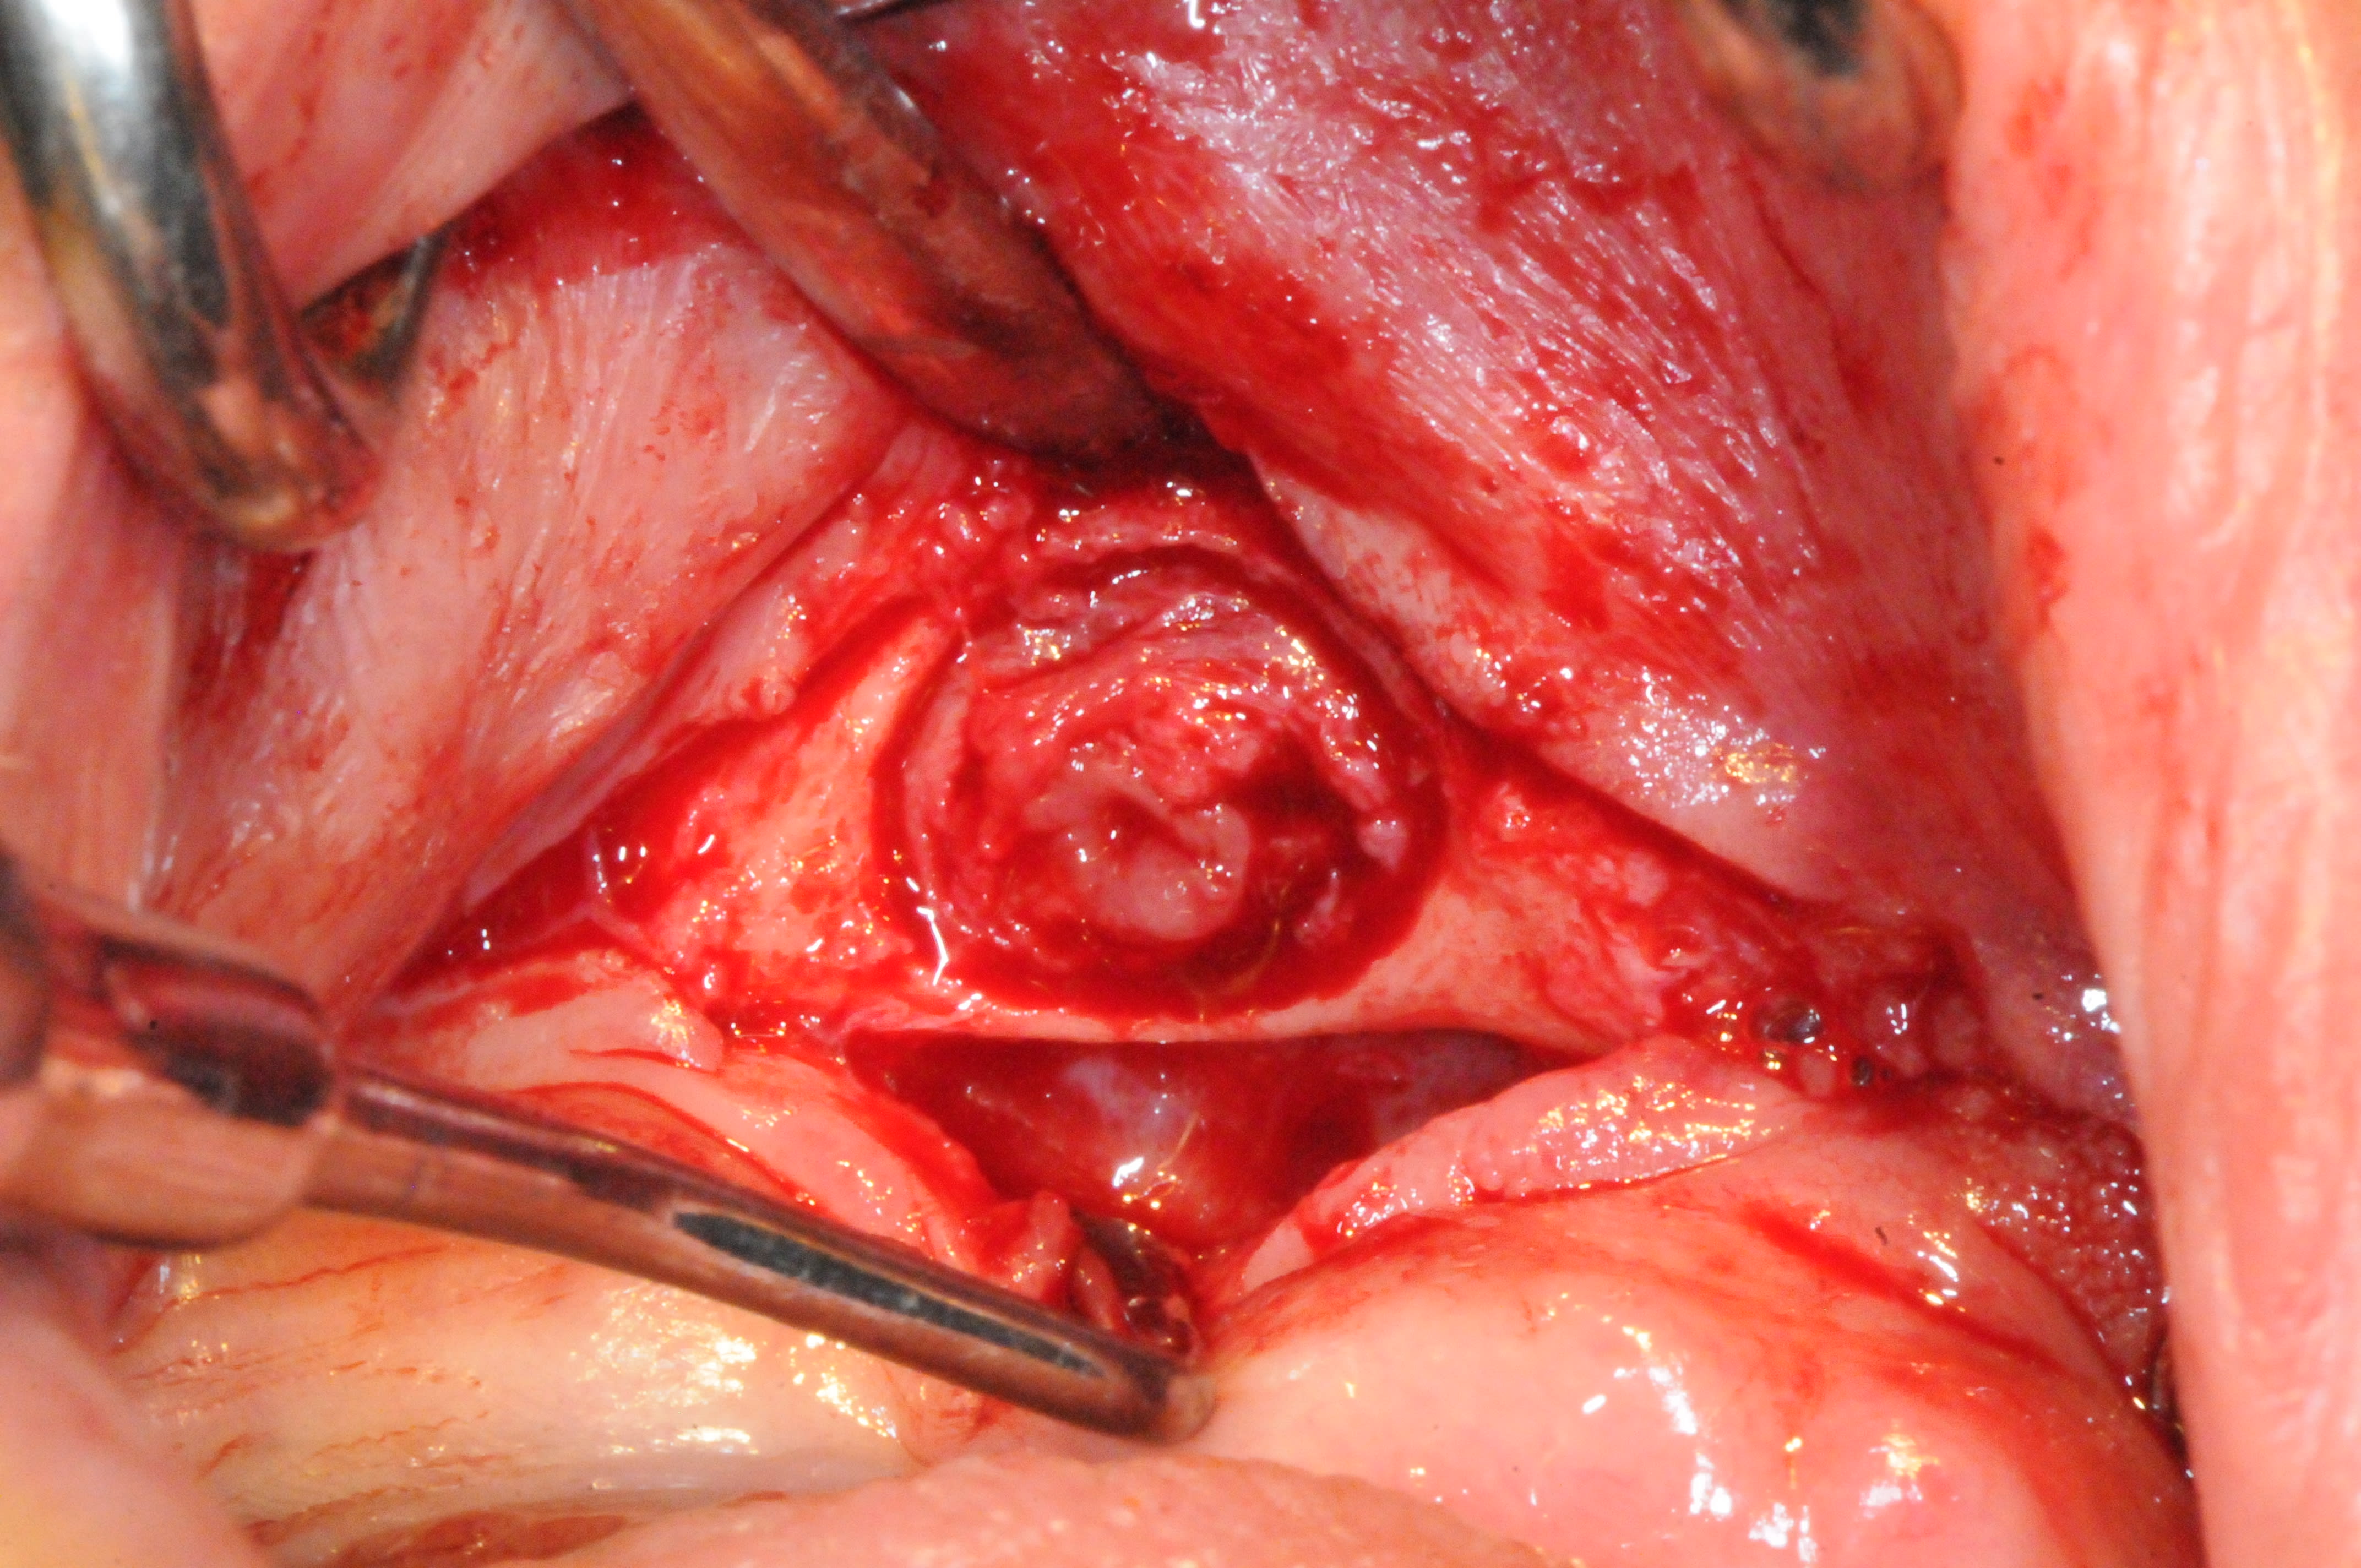

intervention pour retirer le kyste et curetage avec reconstruction osseuse par ROG ( bioos, membrane et tutti quanti..)

toi tu utilises une règle, les vétérinaires les enlève aussi par paire, et utilisent plutôt une pièce 😊. Quand on voit les photos de tes 2 kystes on pourrait penser à ça 😊